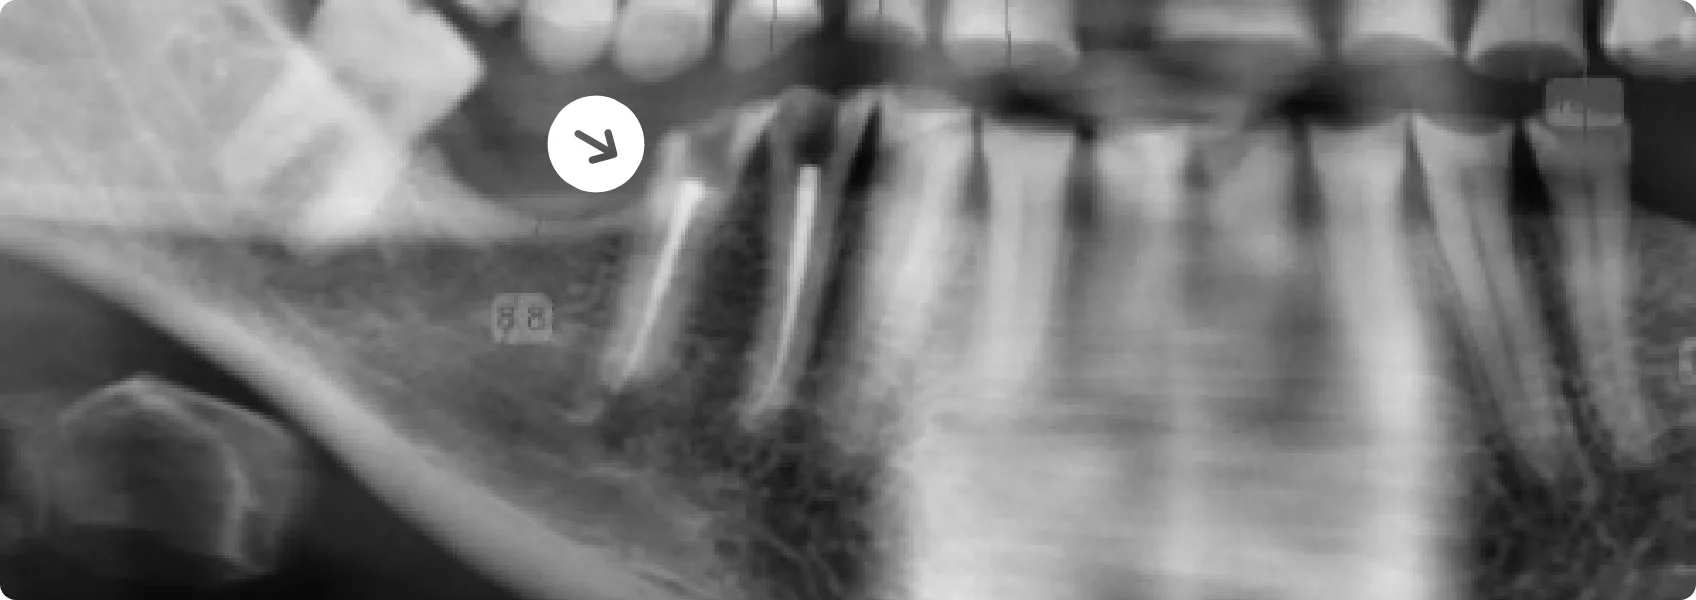

Implantacją zajął się nasz chirurg szczękowo-twarzowy dr n. med. Piotr Chomik. Wstępne zdjęcia RTG pozwoliły mu ogólnie ocenić sytuację i przybliżoną wysokość kości. Do precyzyjnego i bezpiecznego zaplanowania implantacji potrzebował jednak dodatkowej tomografii komputerowej (CBCT).

Ten zaawansowany skan 3D dostarcza nieocenionych informacji. Pokazuje nie tylko wysokość, ale przede wszystkim szerokość i kształt kości w miejscu planowanego wszczepu, co jest niezbędne do dobrania implantu o idealnym rozmiarze.

CBCT umożliwia także ocenę gęstości tkanki kostnej — na tej podstawie doktor Piotr określa, czy implant będzie stabilny i nie wypadnie. Dodatkowo pozwala chirurgowi precyzyjnie zlokalizować nerwy — to szalenie istotne, aby trwale nie uszkodzić czucia w twarzy!

Dzięki pełnej diagnostyce zabiegi chirurgiczne w NDC są wyjątkowo dokładne. Chirurg jeszcze przed zabiegiem wirtualnie umieszcza implanty w trójwymiarowym modelu szczęk Pacjenta. Testuje różne pozycje i kąty, aby znaleźć optymalne rozwiązanie, a podczas zabiegu precyzyjnie prowadzi wiertło i implant zgodnie z cyfrowym planem. W ten sposób minimalizujemy ryzyko powikłań.

W dolnym łuku zębowym doktor Piotr wszczepił łącznie cztery implanty.

Tak zaplanowany zabieg chirurgiczny przebiegł bez przeszkód, a wszystkie implanty na finalnym zdjęciu RTG wyglądają na stabilne i jakby radosne. :-)